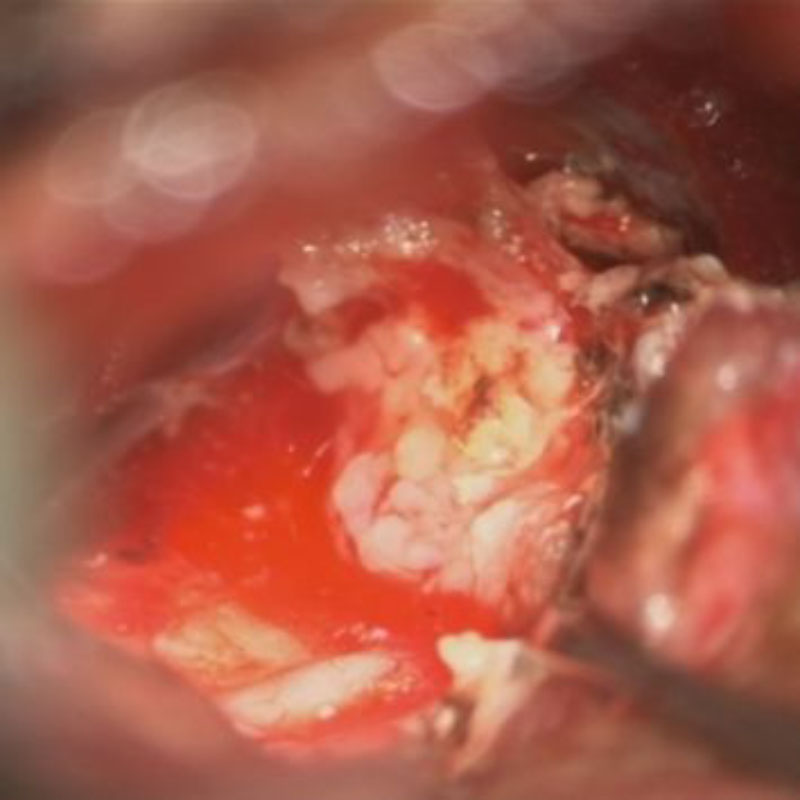

頭蓋咽頭腫

頭蓋内腫瘍摘出術

No.’25_96  摘出 中

No.’25_96 摘出 後